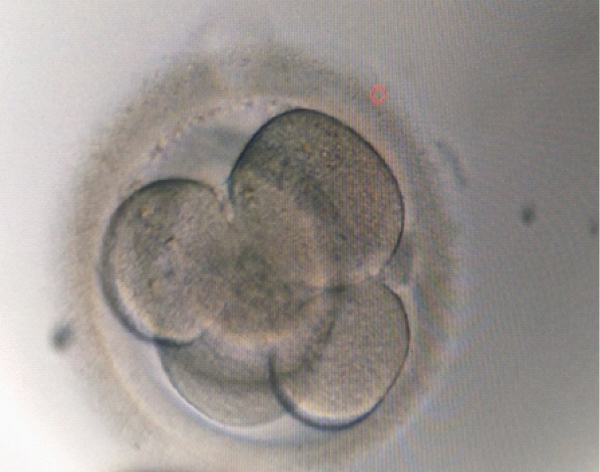

On day 2, the embryo was a four–cell grade one, reaching six–cells grade one on day 3, when it was transferred to the uterine cavity (Figure 1). The embryo culture was completed adopting a sequential preequilibrated medium (Vitrolife G–series) as follows. Firstly, the fertilized oocyte was placed into a 20–microliter drop of G–1™ media, covered by light paraffin oil, sterile filtered (OVOIL–Culture Oil, Vitrolife, Sweden) [15]. On the morning of day 3, the embryo was transferred from the G–1™ micro droplet to a 20–microliter droplet of G–2™ medium, and kept in culture until 3 hours, when the embryo transfer was performed. We hereby report a compelling case in which an ongoing pregnancy with fetal heartbeat was obtained from the only oocyte collected after COS with immotile frozen sperm. The embryo replacement was completed under transabdominal ultrasound guidance using a soft transfer catheter (Wallace TM Classic, Cooper Surgical, USA). We started the luteal phase support with 90mg progesterone vaginal gel twice a day (Crinone 8%, Merck) on the evening of egg collection day and continued till the 8 ®gestational week, a tablet of baby Aspirin 75mg daily with folic acid one tablet a day was added.

Figure 1:Embryo transferred on day 3.